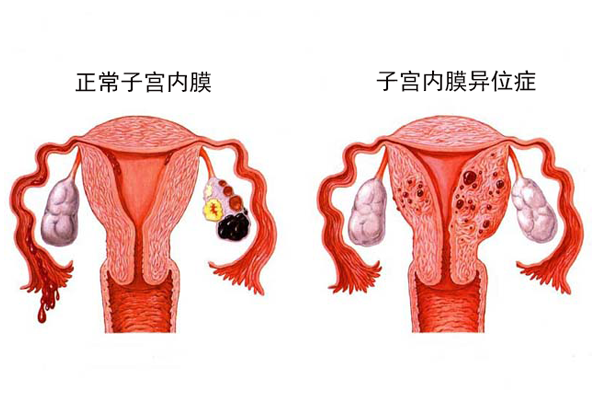

试管婴儿的重要的适应症之一是子宫内膜易位症,子宫内膜异位症引起的疼痛,通常是难以忍受的巨痛,虽然可以通过手术、激素、药物治疗来部分缓解,但残留的疼痛感还是会与日俱...

顾名思义,子宫内膜异位症就是本来应该长在宫腔的子宫内膜异位生长在不该长的地方,如卵巢表面、盆腔腹膜表面、直肠、膀胱或直肠阴道隔等。奇妙的是,“流窜”到其他部位的内...

为什么患有子宫内膜异位症的女性需要试管婴儿技术?子宫内膜异位症的特征性表现是子宫内膜腺体及其基质存在于宫腔以外的部位,通常会导致不孕,虽然两者之间的关系尚存争议。...

子宫内膜异位症在做试管的人群中很常见,对于处于生育年龄中的女性来说,子宫内膜异位症的患病率估计为6%-11%。对于不孕不育妇女来说,子宫内膜异位症的患病率估计为2...

子宫内膜异位症是一种多数发牛于女性盆腔中的常见病理过程。虽然对于子宫内膜异位症的治疗已积累了丰富的临床经验和大量实验研究,但其发病机制和治疗方法仍然存在很多不确定...